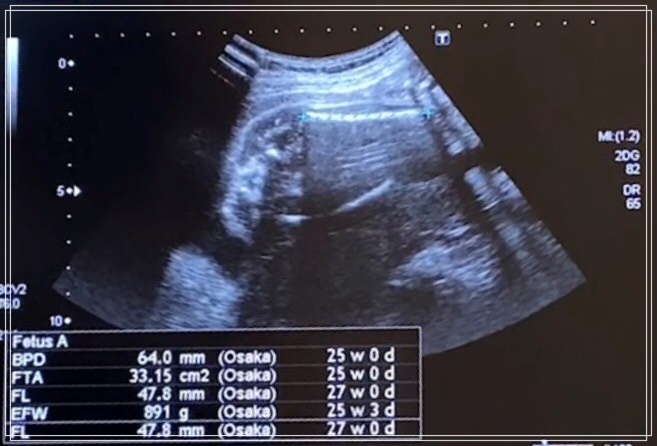

チビきっきんは、頭のサイズが64mmで体重が891gで順調に育ってました。

今回はエコーの様子もご紹介します。

頭の大きさ、体重もわかるのがすごいなと思いました。

順調に育っているとも検診の結果言われましたので安心できました。

エコーの段階で鼻と唇がしっかりしてていいねと言われました。

唇も割れていないとも言われたので安心できました。